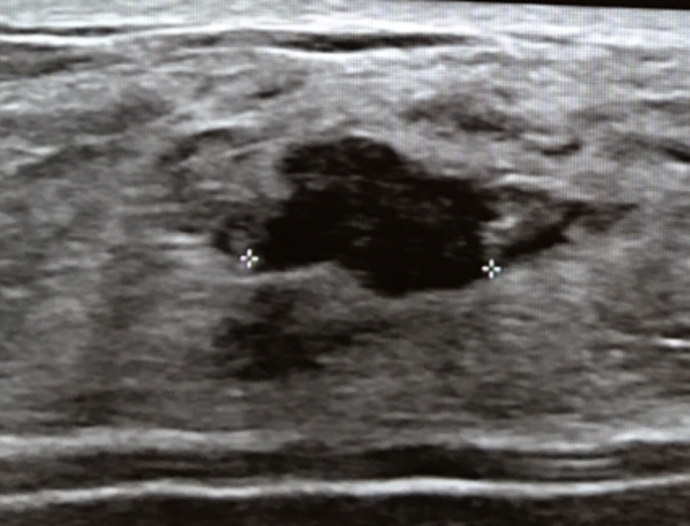

Opinion - Cancer or Fibroadenoma? Pics of ultrasound

history of fibroadenomas but new ultrasound picked up irregular lesion that doc is getting me to do biopsy. Any thoughts?

history of fibroadenomas but new ultrasound picked up irregular lesion that doc is getting me to do biopsy. Any thoughts?

My past fibroadenomas have never looked like this one - they were oval and smooth in shape hence why I thought I'd gather some feedback from people who have tested.